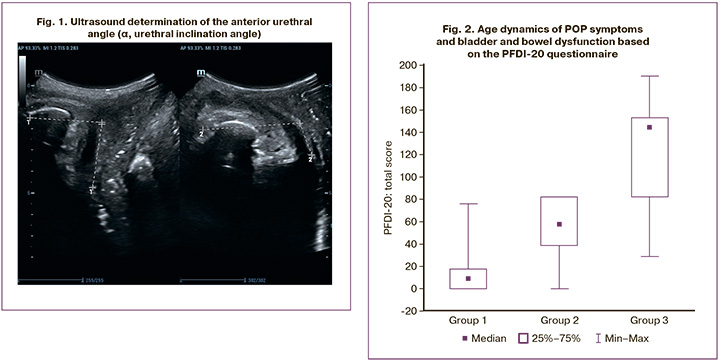

Ultrasound assessment of urethral topography confirmed the significant influence of age on the parameters associated with mobility of the anatomical structures of the pelvic floor. Our study revealed that women in Group 2 showed significant changes in angle α (Δ inclination angle α = 18.3 (4.7)°; in Group 3, angles α and β demonstrated more pronounced changes: Δ angle α was 28.8 (15.0°), and angle β during the Valsalva maneuver increased to 150.6 (13.7°) (Fig. 1).

Evaluation of POP symptoms and bladder and bowel dysfunction based on the PFDI-20 questionnaire is shown in Figure 2. In group 1, the median score was 9.4 [0.0; 17.7]; in group 2, the median was 57.3 [38.5; 82.3]; and in the 3rd group – 144.8 [82.3; 153.1]. A statistically significant increase in the final score was observed when studying the dynamics of the obtained indicators. The Kruskal–Wallis criterion (H) was 1143.87 (p=0.001) and 2 =840.2 (p=0.001).